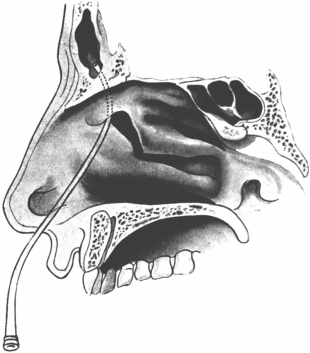

| 345. | Catheterizing the Sphenoidal Sinus | 654 |

| 347. | Radiograph showing a Probe in the Sphenoidal Sinus | 657 |